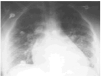

Figura 1. Radiografía de tórax que muestra edema alveolar compatible con SDRA.

Se trata de una paciente en la semana 21 de embarazo que acudió a urgencias con fiebre y dolor lumbar. Con la sospecha de pielonefritis se realizó una ecografía abdominal que evidenció dilatación de vía urinaria y un área hipoecogénica en la cortical del polo superior del riñón derecho. El sedimento urinario mostraba presencia microbiana, leucocituria y proteinuria. La paciente ingresó en urología para que se llevara a cabo una nefrostomía. Se indicó, además, tratamiento con ceftriaxona y aztreonam. Inicialmente la paciente presentaba deterioro del estado general, y la exploración y la ecografía ginecológica confirmaron el buen estado fetal. Se decidió ingreso en la UCI, donde la paciente se encontraba consciente, afebril, taquicárdica (120 lat/min), con una presión arterial de 95/45 mmHg, y taquipneica, con una SatO2 del 90%. La analítica evidenció en la gasometría arterial con oxígeno a 4 l/min: pH, 7,38; PO2, 53 mmHg; PCO2, 36,3 mmHg; HCO3, 21,8 mmol/l; EB, 2,2 mEq/l. El hemograma puso de manifiesto leucocitos, 19,3 x 10% con un 94% de neutrófilos, hemoglobina de 8,7 g/dl y hematocrito del 27,9%. El estudio de coagulación, las cifras plasmáticas de glucosa, urea y creatinina y el monograma fueron normales. La radiografía de tórax evidenció un edema alveolar compatible con SDRA (fig. 1). El primer día la insuficiencia respiratoria progresó con descenso de la saturación, precisando intubación y conexión a ventilación mecánica, con FiO2 de 1 y PEEP +10 cmH2O, PaO2/FiO2: 116. En el ecocardiograma se apreciaba un ventrículo izquierdo normal, con una buena contractilidad y una presión sistólica pulmonar de 38 mmHg. En el sexto día de ingreso, con buena evolución, se extubó, presentando laringospasmo, que no respondió al tratamiento médico, precisando reintubación y posterior traqueostomía. Los cultivos fueron negativos. A partir de ese momento no aparecieron nuevas complicaciones por lo que se trasladó a planta. En la semana 31 nació por cesárea un niño sano.